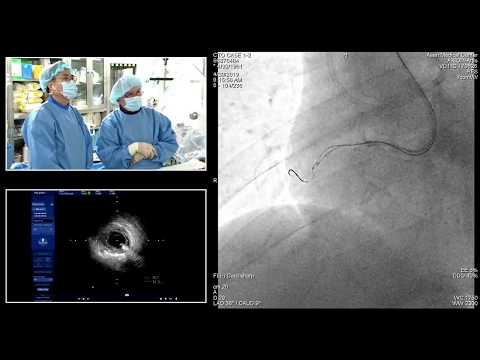

[TCTAP 2018] Master the CTO - Opening Remark & Live Case Session I

[TCTAP 2018] Master the CTO - Live Case Session II

[TCTAP 2018] Master the CTO - Live Case Session III

[TCTAP 2018] Master the CTO - Live Case Session IV

[COMPLEX PCI 2022] Complex PCI Master Class 3: CTO

4th INTERNATIONAL CARDIOLOGY CME - CTO PCI - MASTER THE COMPLEX